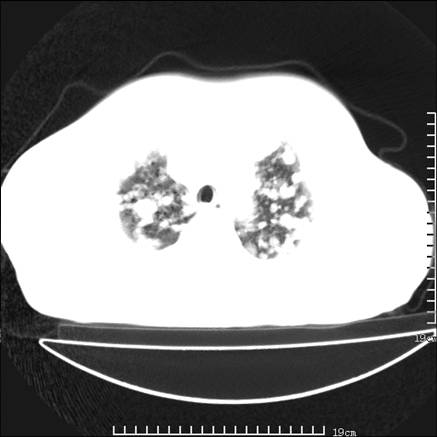

张男,75岁,干咳半年余,小便不利二年,b超检查前列腺增大,未见明显肿块;前列腺癌血生化检查多项指标明显增高。

双肺内多发转移瘤,纵膈淋巴结转移。来源前列腺?建议盆腔mri进一步检查。

双肺转移满了。

两肺广泛转移瘤。